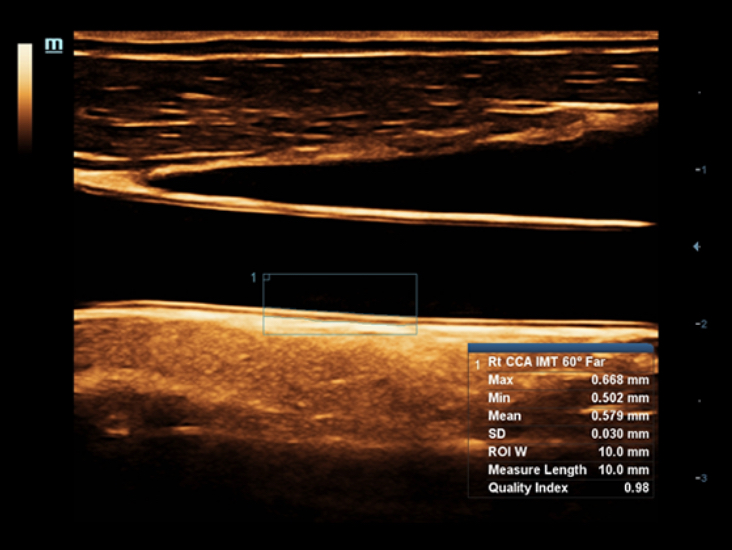

X-Insight adalah solusi untuk visualisasi lebih lanjut.

Dengan pemahaman mendalam atas kebutuhan pelanggan, DC-60 Exp dengan X-Insight dirancang untuk menyajikan efisiensi tinggi dengan pencitraan yang presisi, yang didukung oleh eXpress Clarity, eXceptional Intelligence, dan eXceeding Experience.